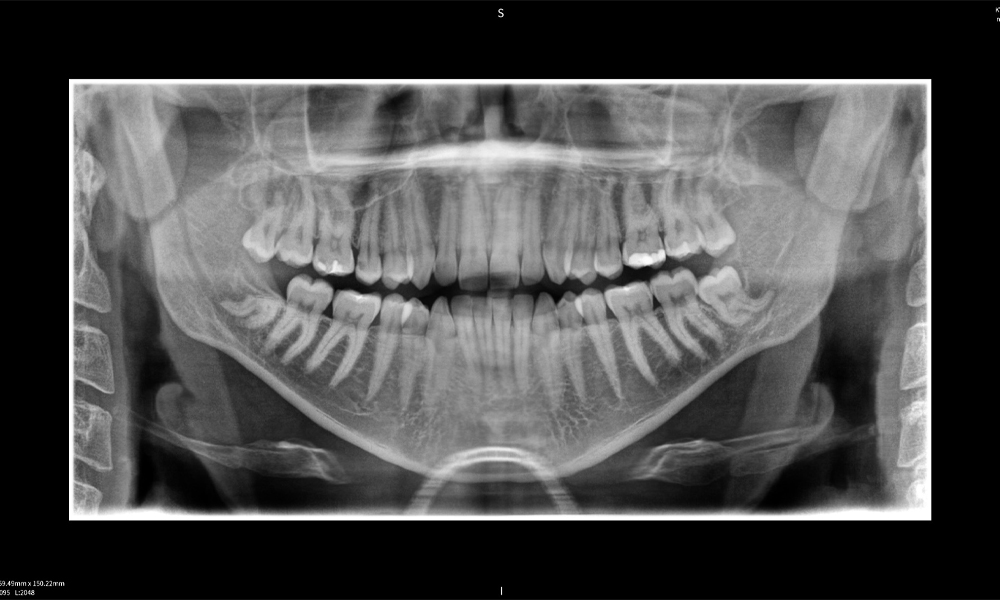

Abbildung e: Panoramaröntgenaufnahme dient der initialen Beurteilung und zeigt die allgemeine Zahnstellung sowie mögliche pathologische Veränderungen auf. Insbesondere ist auf der rechten Seite (Zahn 48) die Situation nach einer Kronenamputation durch einen externen Behandler ersichtlich. Die beiden stark gekrümmten Wurzeln verbleiben in enger topographischer Beziehung zum Nervus alveolaris inferior im Knochen. Dies deutet auf eine bewusste Entscheidung zur Vermeidung eines erhöhten Risikos einer Nervenläsion während einer vollständigen Extraktion hin und stellt einen klinisch relevanten Befund dar. Zusammenfassend liefern die CBCT-Aufnahmen mit Seethrough Max entscheidende Informationen über die komplexe Anatomie und die kritische Beziehung zwischen den Weisheitszähnen und dem Nervus alveolaris inferior. Diese detaillierte präoperative Diagnostik ist unerlässlich für die sichere und erfolgreiche Durchführung chirurgischer Eingriffe im Unterkieferbereich.